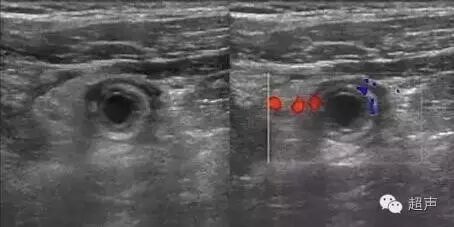

阑尾蚯蚓状中度肿大,管腔扩张,腔内可见积脓暗区,内有散在片絮状光点,伴粪石者可见强光团。其周围可伴少量渗出液无回声暗区。阑尾壁上及周围组织血流信息丰富。

阑尾壁连续性中断。阑尾区探及一形态不规则,部分中央呈弱回声环状元回声带,无回声区中央为实体回声。形如“牛眼征”。脓肿周围探及丰富血流,盲肠蠕动减弱及肠问积液。